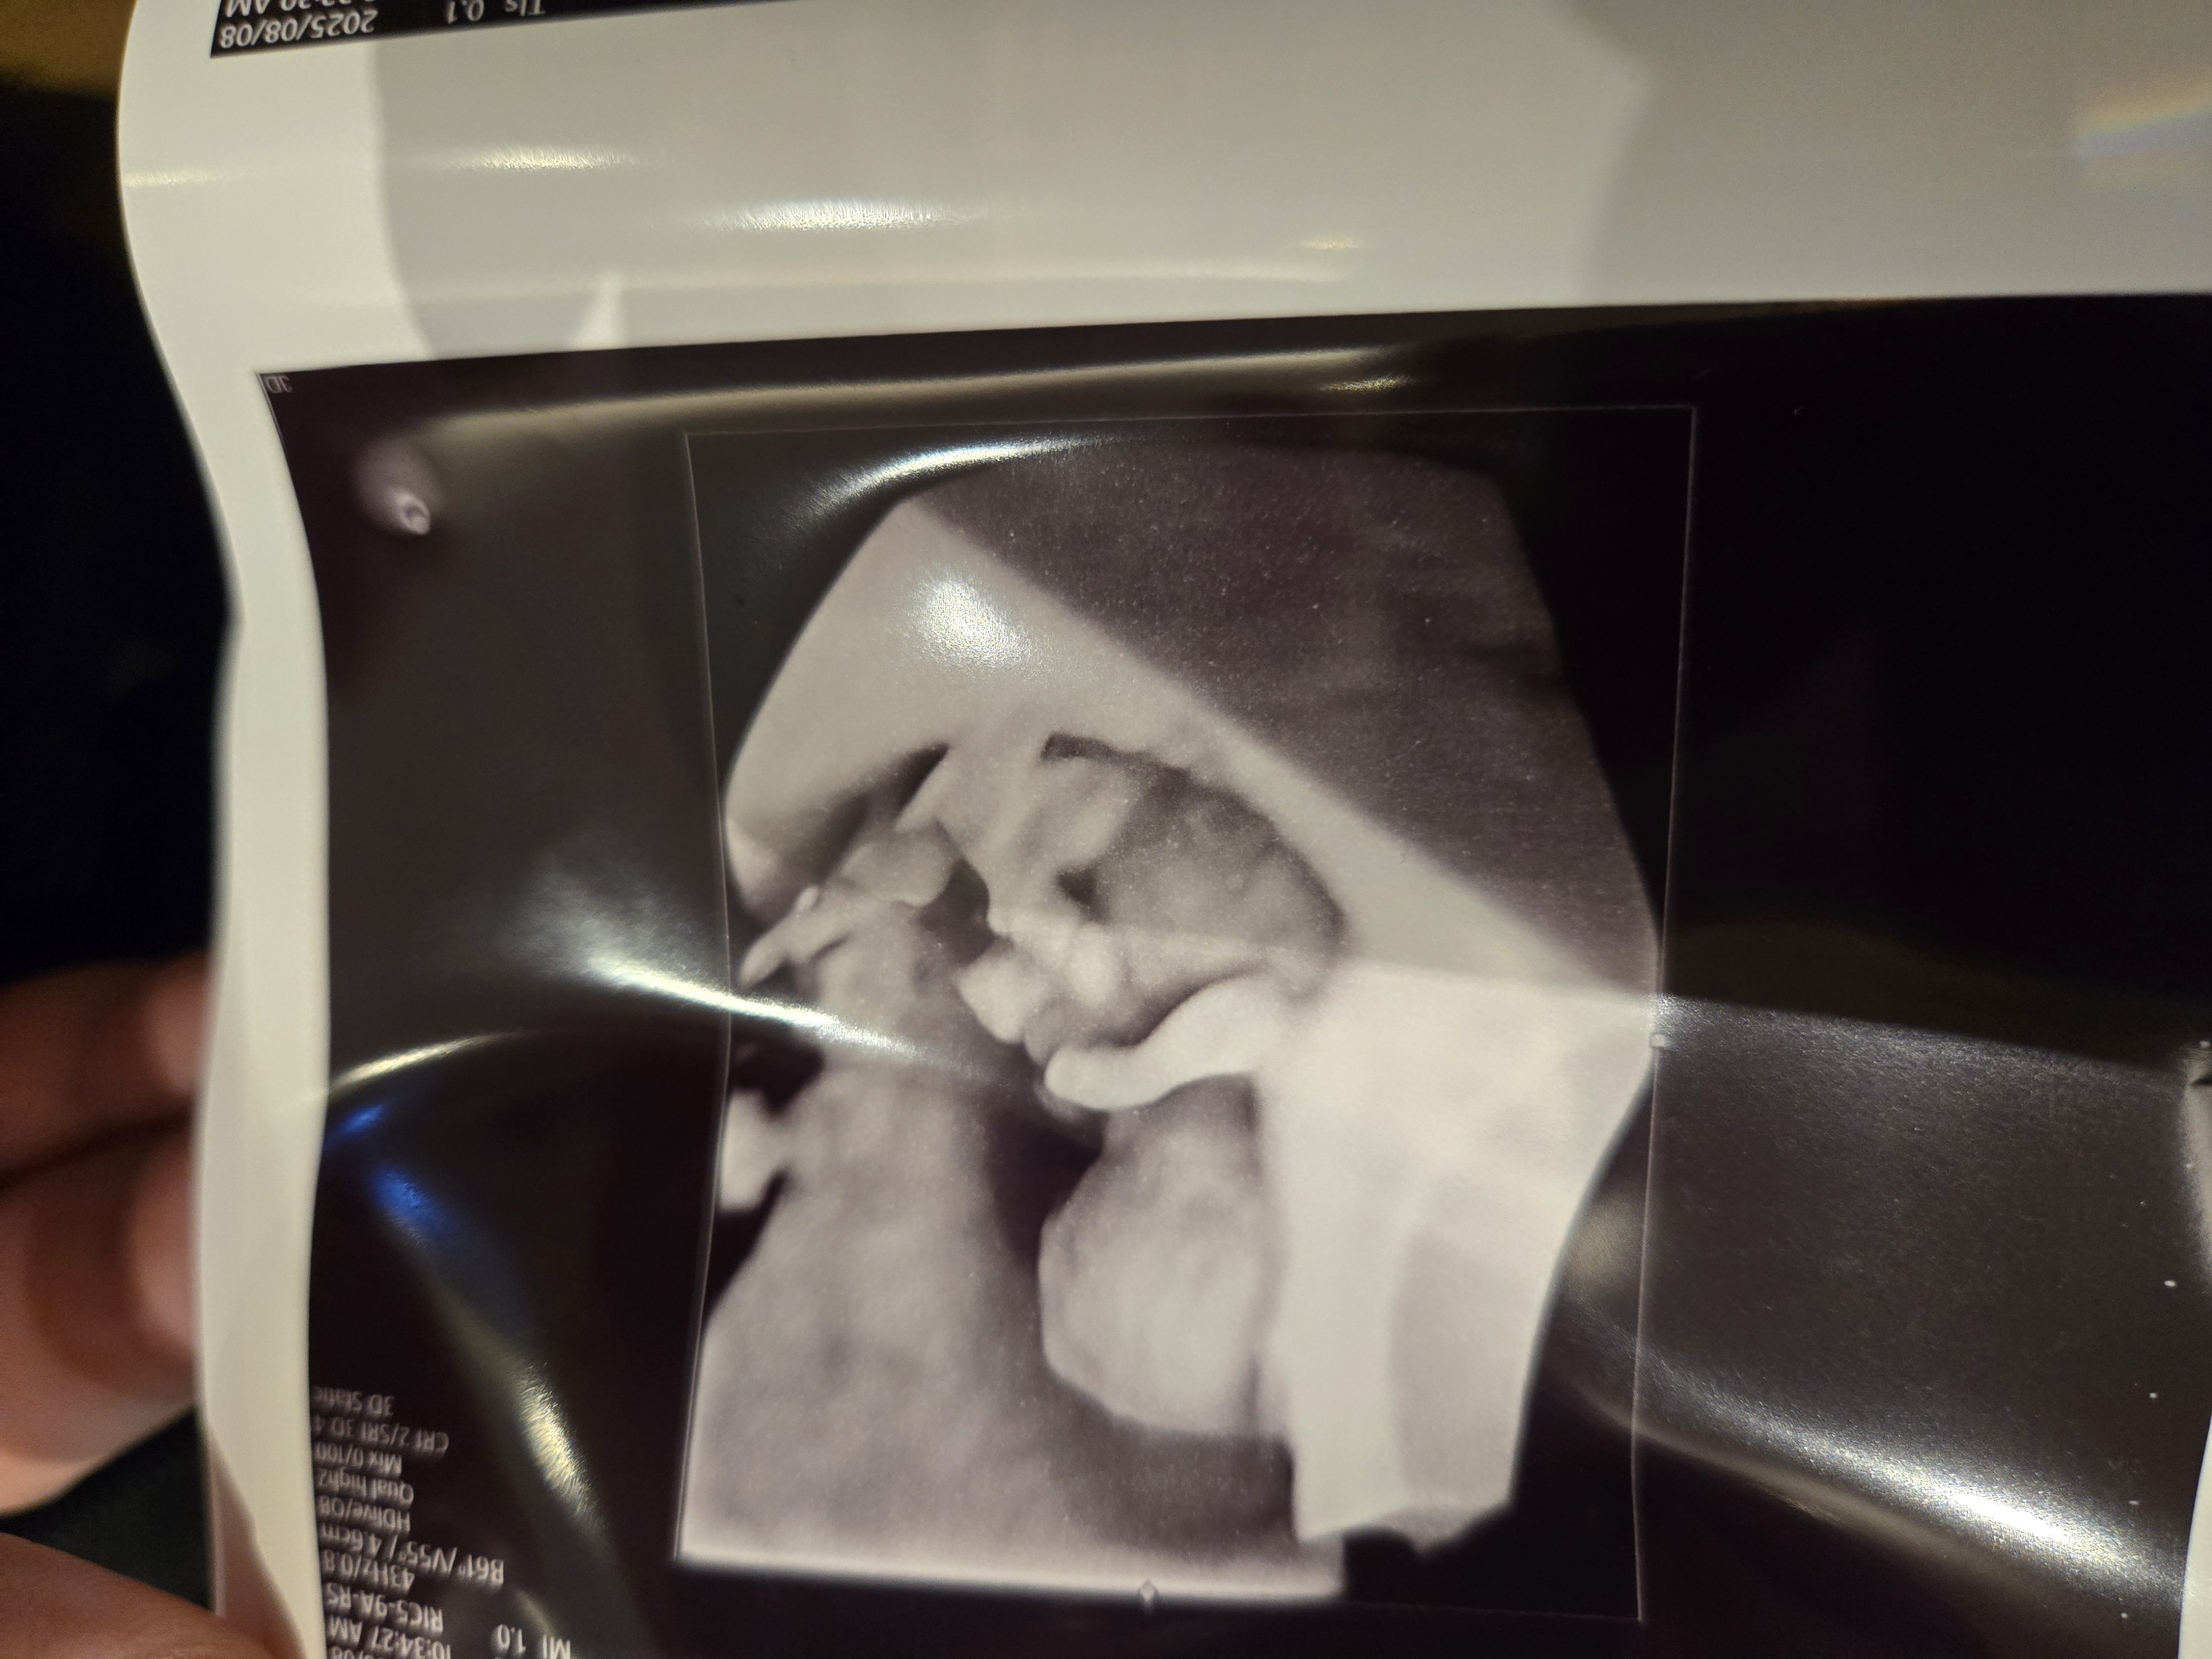

| 치료 도중 느꼈던 가장 기뻤던 순간과 절망적인 것들은 무엇인가요? 잊지 못할 경험이 있나요? | 가장 기뻤던 순간은 아기 심장 소리를 들었을 때였습니다. 입덧 같은 제가 확인할 수 있는 증상이 아직 없을 때라 제가 확인을 못하니 아기가 잘있는지 걱정됐는데, 심장 소리를 듣는 순간 안심이 되었고 눈물이 날 만큼 기뻤습니다. 이경훈 원장님과 간호사 선생님들께서 늘 친절하고 따뜻하게 대해주셔서 치료 과정 내내 절망적인 기억없이 감사한 마음이 더 컸습니다. |